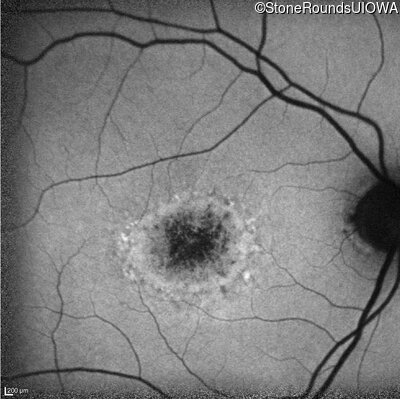

AR Stargardt Disease (IIA)

Age at visit:

53 years

OD

OS

20/200 +2

20/50 -1

AR Stargardt Disease

ABCA4

IVS40+5 G>A

Gly1961Glu GGA>GAA

AR